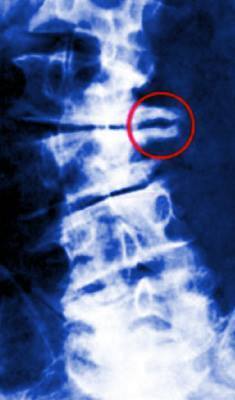

Bico de Papagaio (Osteófitos)

Os Osteófitos são pequenas expansões ósseas que se desenvolvem à volta dos discos da coluna vertebral, que em exames de raio-x se assemelham ao formato de um bico (daí o nome bico de papagaio).

Bico-de-Papagaio-Osteofitos

Bico de Papagaio – Osteófitos